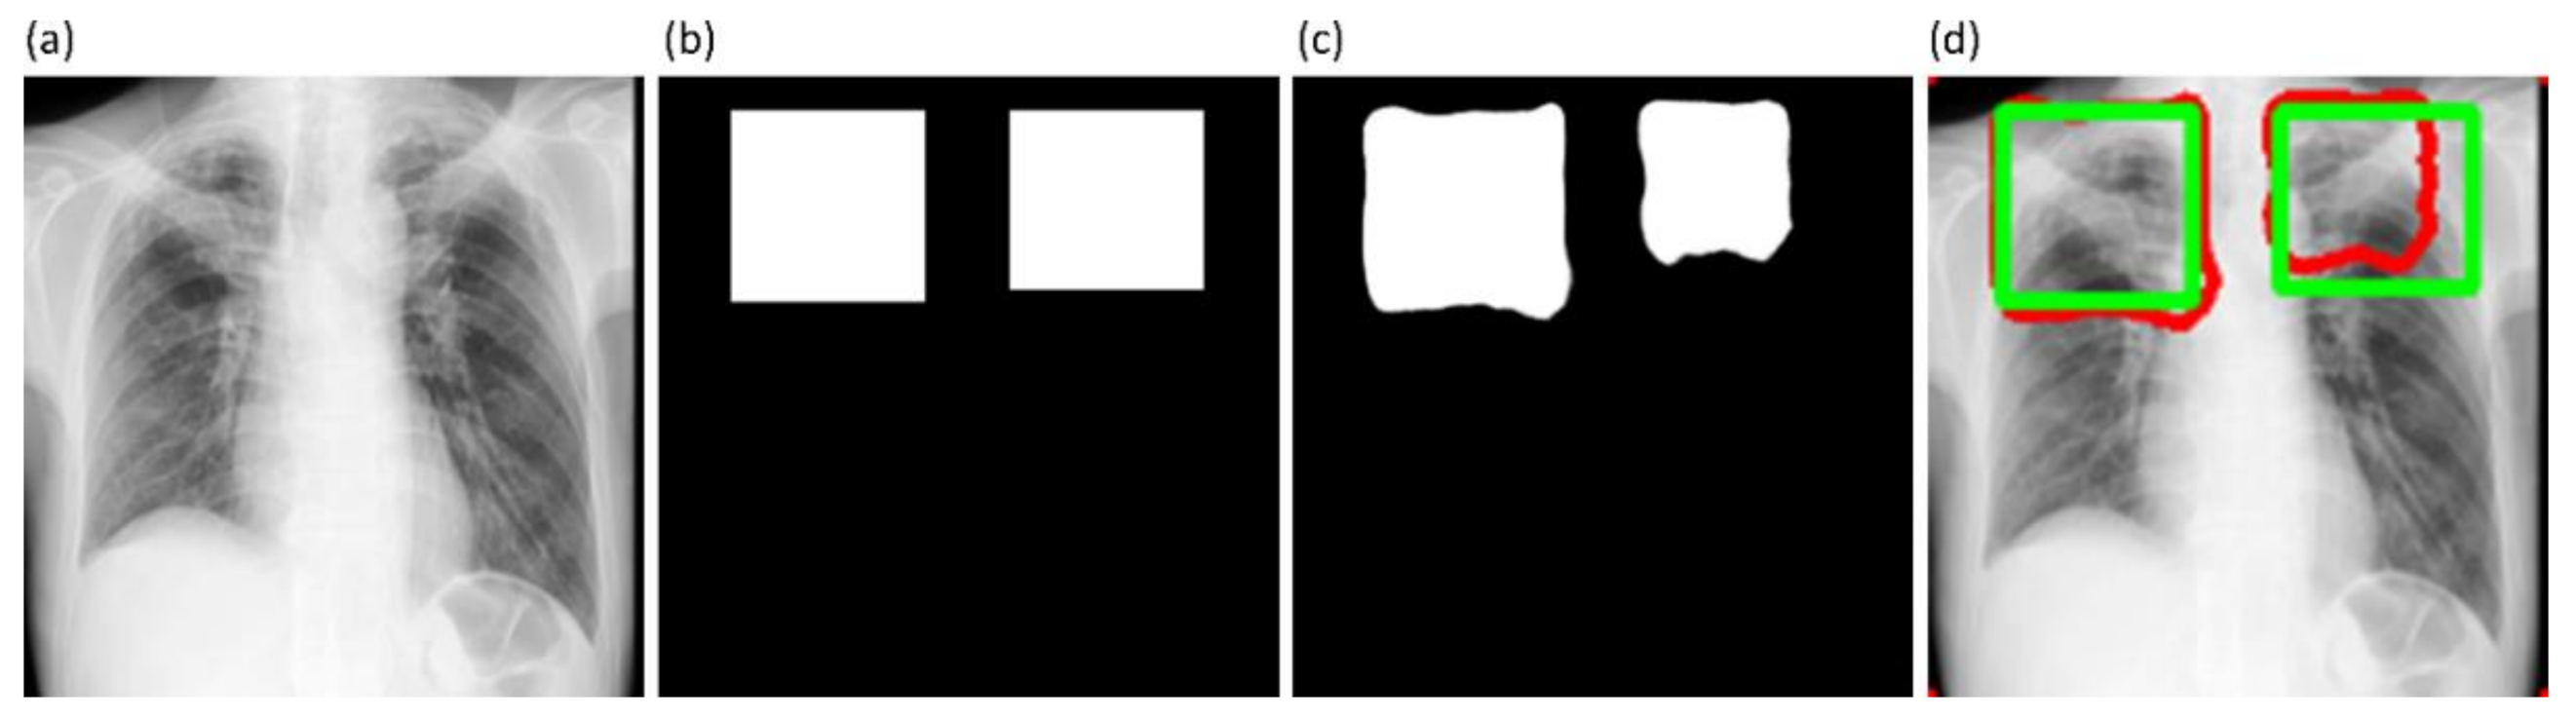

Figure 6 shows instances of TB-consistent

ROI annotations made by the radiologists and the STAPLE-generated consensus

ROI for a sample CXR instance from the Shenzhen TB CXR-Subset-2 and Montgomery TB CXR collections respectively.